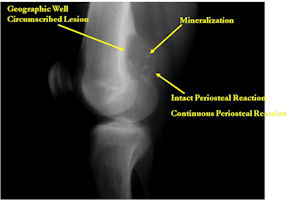

Plain X-rays:

- Geographic, circumscribed lesion usually around 5cm in size.

- There may be expansion of bone, cortical thinning and cortical breakthrough. A soft tissue mass may accompany this lesion but the soft tissue component is usually contained by the periosteum.

- The periosteum remains intact around the soft tissue component. Might need a CT scan to detect the subtle calcification (Egg Shell Rim of Calcification) associated with an intact periosteal reaction

- The lesion may be entirely radiolucent but usually shows some degree of mineralization. Mineralization may appear stippled like cartilage but do not see chondroid pathologically. Mineralization is sometimes better detected on a CT scan rather than an x-ray.

- Usually less surrounding sclerosis than an osteoid osteoma.